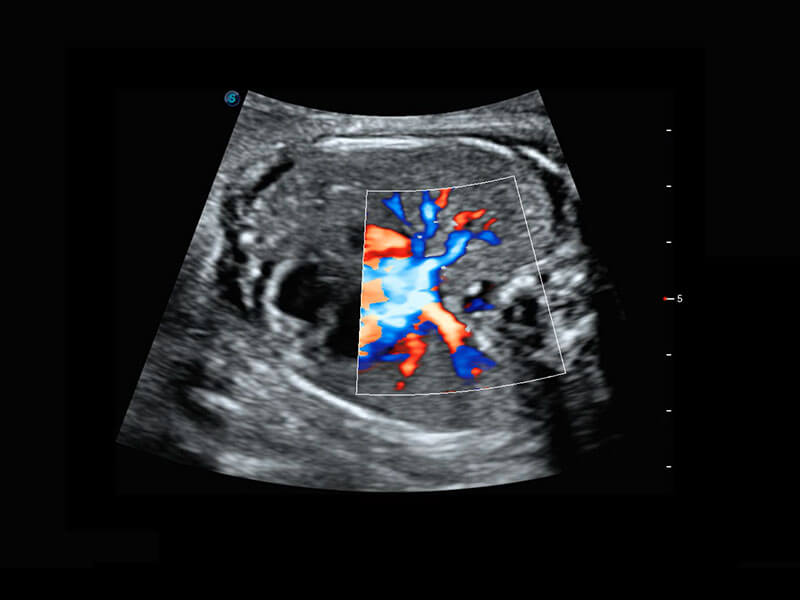

新生儿肝血管癌

P60搭载宽频带线阵探头、宽景成像、弹性成像技术,为您提供乳腺应用方案。P60支持高频相控阵探头、线阵探头、腹部高频探头、腹部微凸探头等,丰富的探头群搭载敏感的彩色血流成像,适用于新生儿多种脏器检测要求,满足新生儿筛查需求。